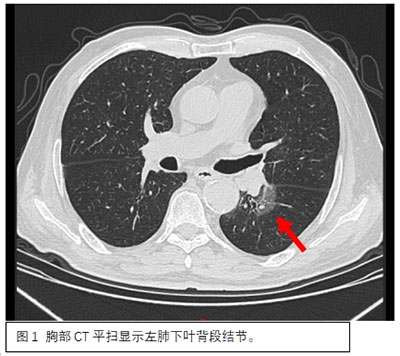

患者因体检发现肺部阴影到北京胸科医院就诊治疗。据胸外一科主任阮军忠介绍,患者左肺有2个需要治疗的高危结节,大者位于左肺下叶背段,最大径达30mm(图1),另一个结节位于左肺上叶尖后段,直径为8mm(图2);同时,患者高龄75岁,合并多年高血压、冠心病、糖尿病史。若均通过外科手术切除高危结节,则会损失较多肺功能,且手术创伤大、时间长,围术期心血管事件风险明显升高。根据患者病情,胸外一科阮军忠团队与CT介入科主任侯代伦及副主任医师王东坡团队联合进行了术前讨论和准备,并与患者家属充分沟通后,制定了治疗方案,决定在同一天,先由王东坡团队于放射科局麻下行CT引导下经皮穿刺微波消融手术治疗左肺上叶尖后段结节(图3),随后由阮军忠团队于手术室全麻下行胸腔镜下左肺下叶背段切除术(图4)。